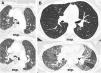

La TC torácica en espiración es una técnica complementaria de la inspiración que aporta valiosa información fisiológica y puede ser más sensible que las pruebas de función respiratoria para detectar atrapamiento aéreo. Tiene múltiples indicaciones, entre las más frecuentes están la enfermedad obstructiva de la vía aérea producida por bronquiolitis obliterante, asma, síndrome de Swyer-James, traqueomalacia, neumonitis por hipersensibilidad o sarcoidosis. En alguna de ellas, como la bronquiolitis obliterante, la TC espiratoria puede ser la única técnica de imagen que detecta alteraciones en las fases iniciales. Si queremos que sea de utilidad diagnóstica, hay que asegurarse de que el estudio tenga calidad suficiente. Para ello se recomienda explicar al paciente en qué consiste la prueba, emplear instrucciones precisas y realizar un breve entrenamiento antes de iniciar la adquisición. En este trabajo sugerimos estrategias para optimizar la técnica y proponemos un algoritmo para interpretar los hallazgos radiológicos en el contexto de la patología obstructiva pulmonar.

Expiratory CT scan is a complementary technique of inspiratory CT that provide valuable physiological information and may be more sensitive to detect air trapping than pulmonary function tests. It is useful in many obstructive airway diseases, including obliterative bronchiolitis, asthma, Swyer-James syndrome, tracheomalacia, hypersensitivity pneumonitis and sarcoidosis. In obliterative bronchiolitis, expiratory CT scan may be the only imaging technique that shows abnormalities in the early phase of disease. In order to obtain a good quality study, we should explain the procedure to the patient, use precise instructions and do some practice before image acquisition. Here we describe strategies to optimize the technique and propose an algorithm that help in interpretation of imaging findings in patients with obstructive airway disease.